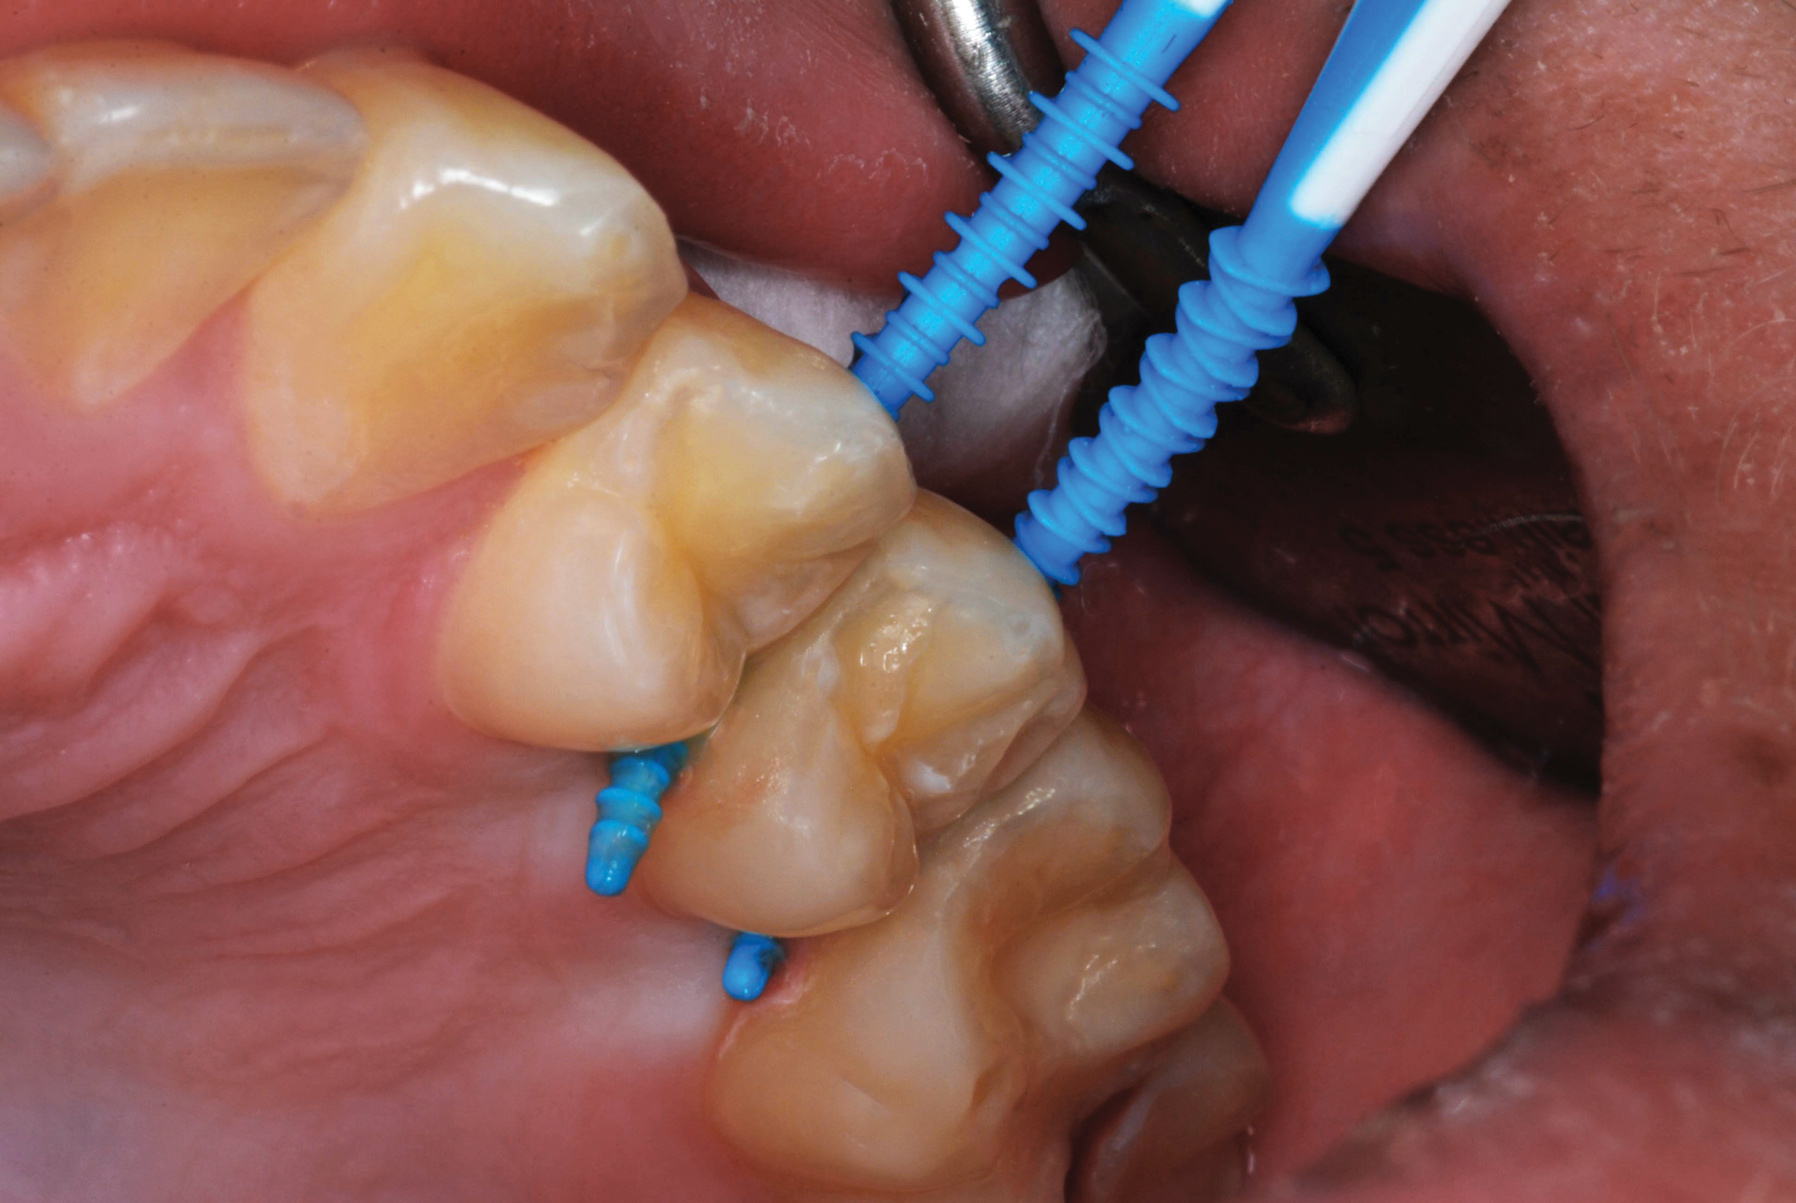

The authors' protocol for insertion of SDF-coated soft dental picks involves isolating the teeth with cotton rolls or other means, flossing the interproximal site to clear food debris and dental plaque, and then inserting a SDF-coated pick (Figure 1 and Figure 2) to saturate the contacting surfaces of the teeth with the fluid. This treatment is painless and requires no anesthetic. The pick should remain in place for at least 60 seconds and can be gently pulled in and out to agitate the fluid for enhanced surface coverage by capillary action. Additional SDF can be wiped on, using a small applicator, above the contact and in the buccal and lingual sluiceways. Excess fluid and any blood elicited may be blotted with a cotton swab. An additional 60-second insertion may be applied in the same way if there is radiographic evidence of a deeper decalcification or caries lesion. With the pick still in place, 5% (or 2.5%) fluoride varnish is painted over the treatment area, and the pick is then withdrawn.

Figure 7 illustrates the use of thicker picks in premolar interproximal sites. Additionally, multiple picks can be used in one quadrant or in one proximal site with good isolation to maximize fluid saturation (Figure 9), which the authors have found to be an excellent time-saving strategy. Preventive or interceptive applications of SDF may also be effectively used in interproximal sites in orthodontic patients (Figure 10).

Fig 7. An example of the use of thicker picks for premolar interproximal sites.

Figure 7